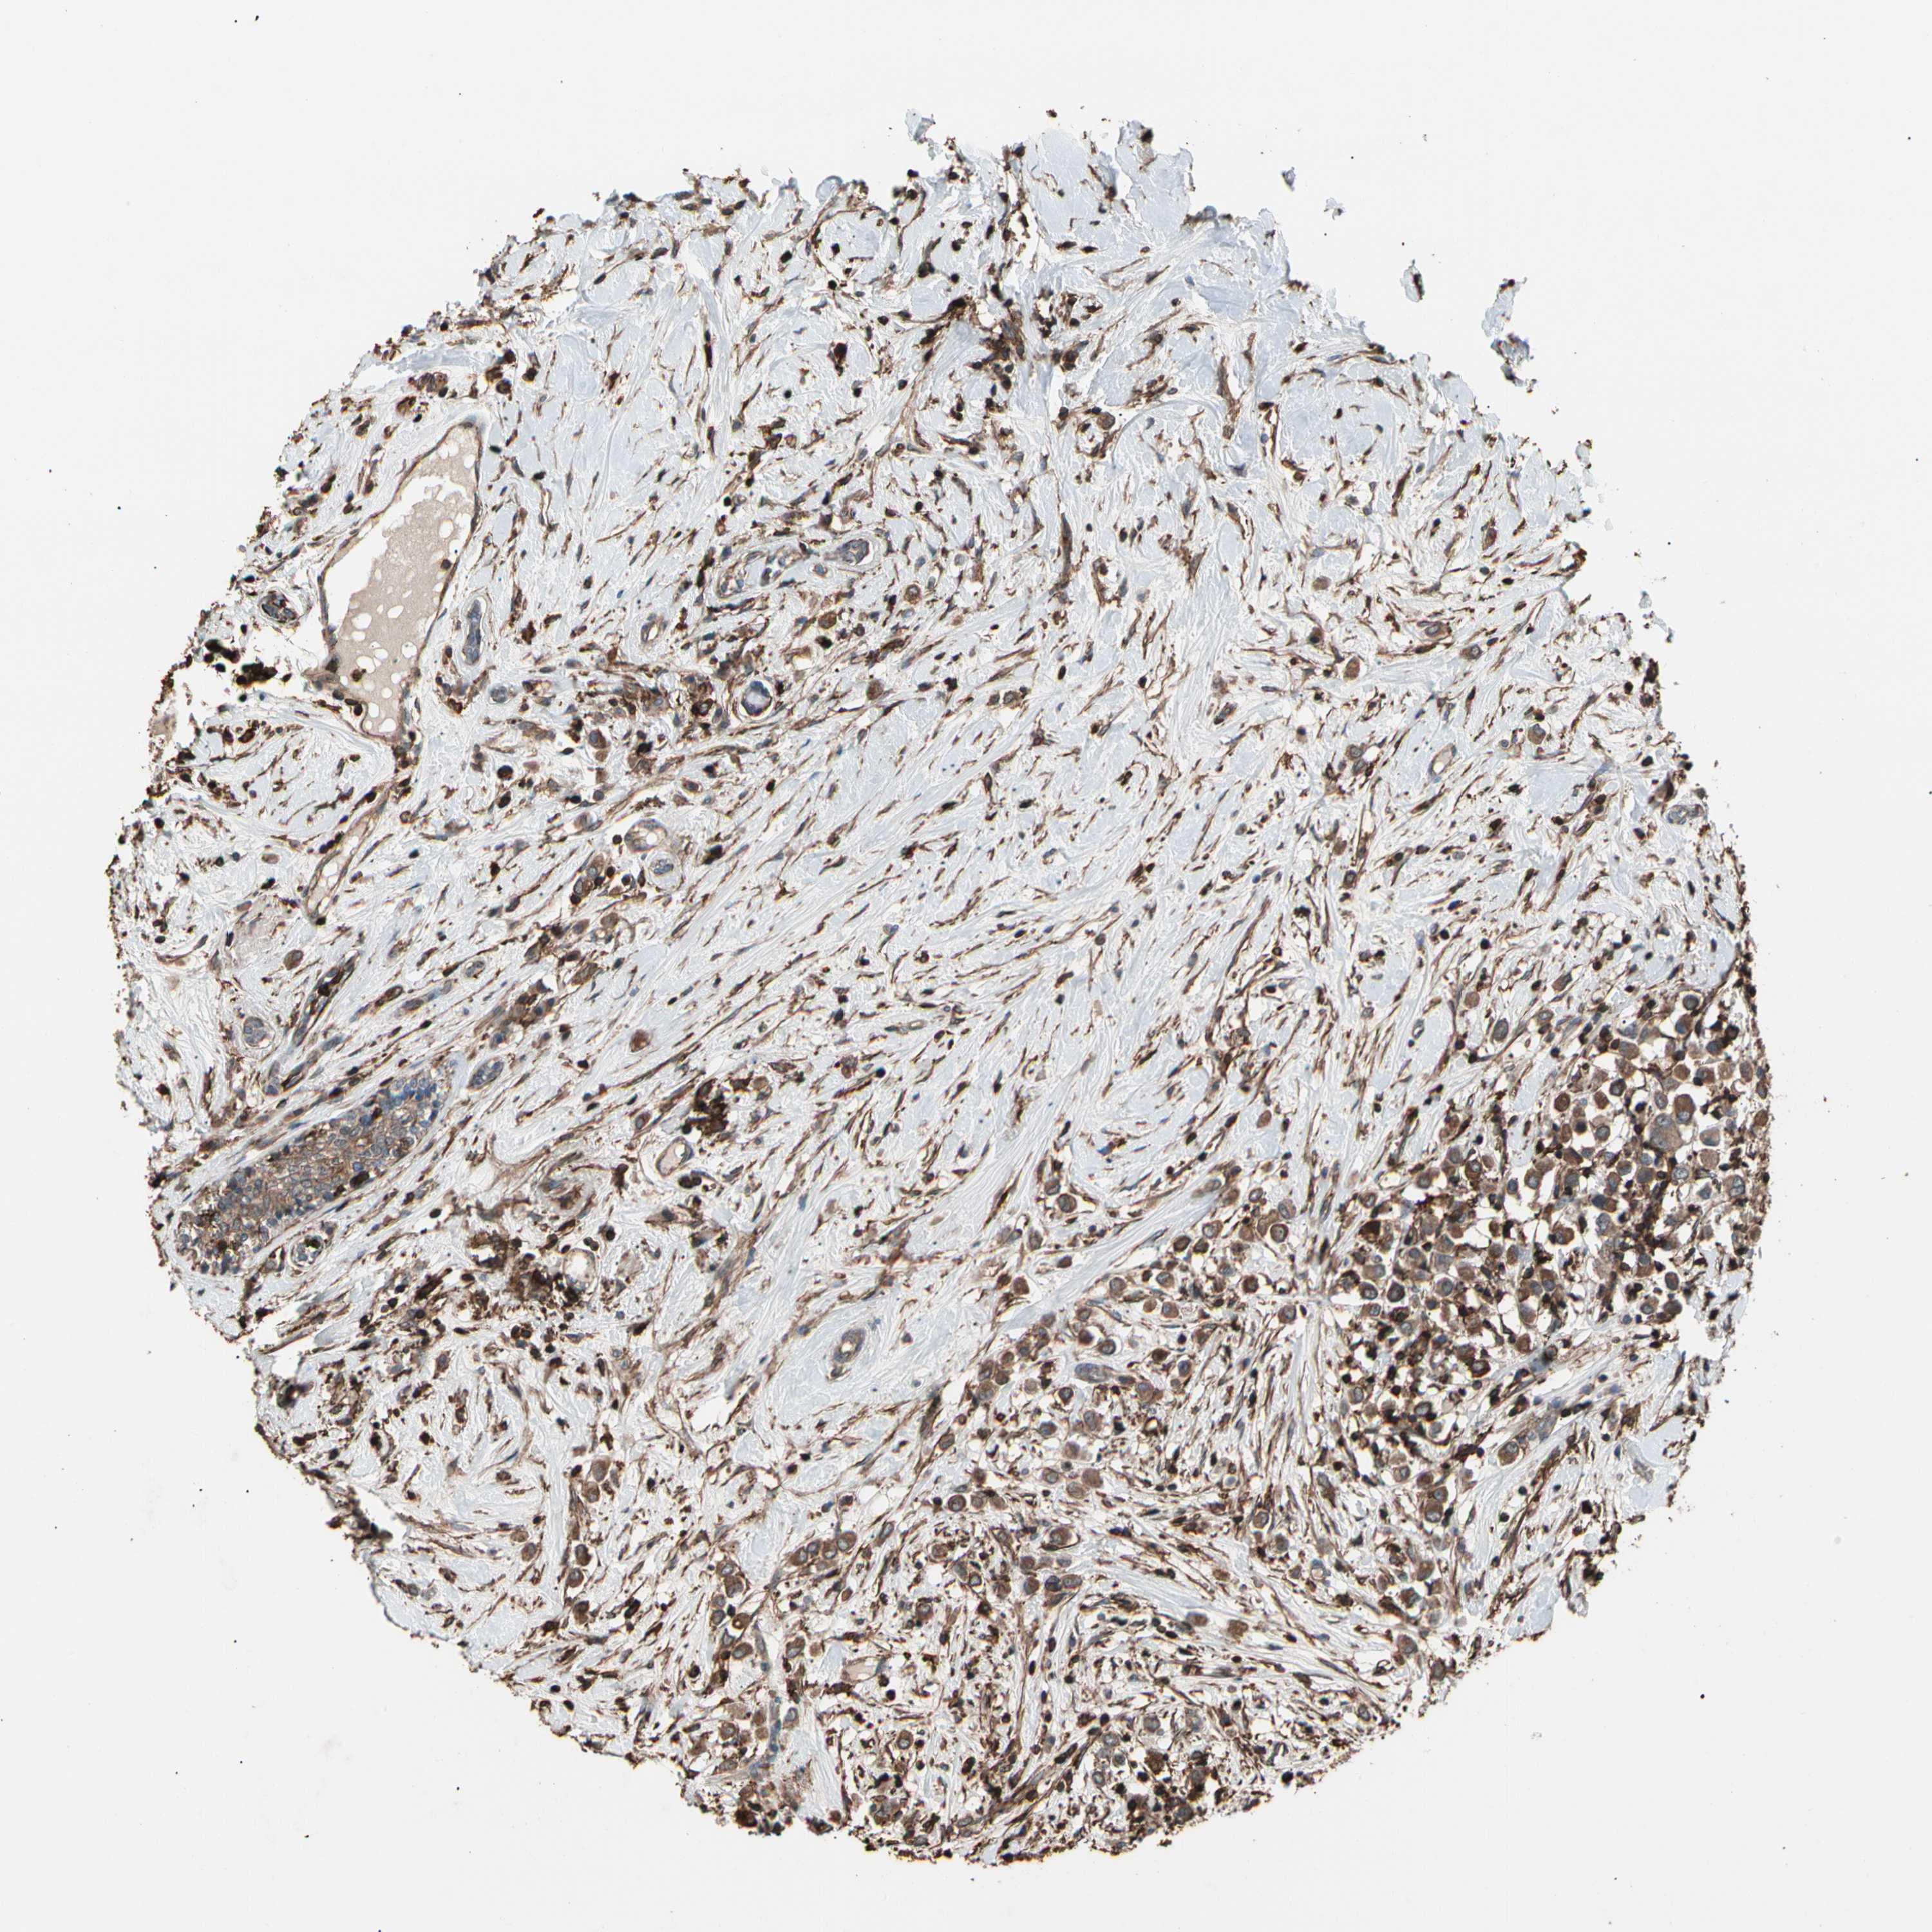

BRCA TCGA BRCA VALIDATION PROTEIN EXPRESSION